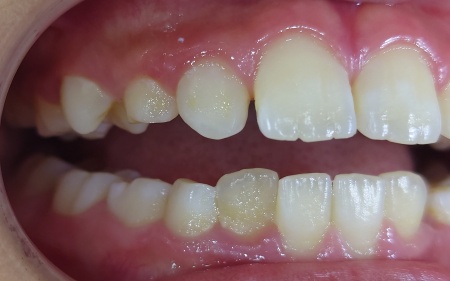

インプラントがあごの骨にしっかりと定着したことを確認してから、型取りを行いインプラントの上に取り付ける人工歯を作製します。

人工歯の種類は治療部位が笑った際に目立つ場所であったため、自然な見た目で強度もあるセラミック製のジルコニアクラウンを選択しました。

その後、完成したジルコニアクラウンを歯茎から自然に生えているように見せるため形や取り付け位置を工夫して装着し、治療を終了しました。